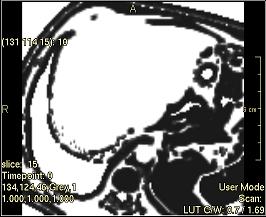

No Filter

The output image is an identical copy of the input image.

../../../Modules/ML/MLFilter2/mhelp/Images/TextureFilterImages/original.jpg